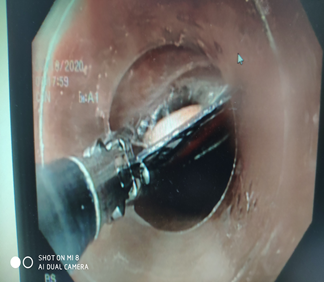

Hình ảnh các bác sĩ và KTV khoa Nội soi đang chích keo tĩnh mạch phình vị trên bệnh nhân

Giãn tĩnh mạch phình vị là tình trạng giãn tĩnh mạch thường gặp ở những đoạn xa tĩnh mạch thực quản và tĩnh mạch phình vị gây ra do tăng áp lực tĩnh mạch cửa, thường xuất hiện ở những bệnh nhân mắc xơ gan. Giãn tĩnh mạch phình vị có thể dẫn đến xuất huyết tiêu hóa với số lượng lớn nhưng thường không đi kèm với các triệu chứng khác. Điều trị giãn tĩnh mạch phình vị chủ yếu bằng cách tiêm keo histoacryl vào búi giãn tĩnh mạch phình vị . Đôi khi người bệnh cũng cần thực hiện phẫu thuật nối thông 2 hệ tĩnh mạch cửa.

- Nội soi chích keo tĩnh mạch phình vị giãn

Hình ảnh búi giãn tĩnh mạch phình vị trước chích keo và đang được chích keo histoacryl